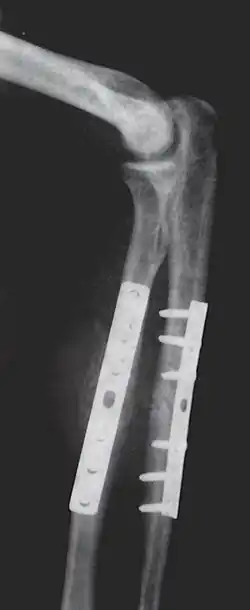

Orthopedic surgery or orthopedics (alternative spelling orthopaedics) is the branch of surgery concerned with conditions involving the musculoskeletal system.[1] Orthopedic surgeons use both surgical and nonsurgical means to treat musculoskeletal trauma, spine diseases, sports injuries, degenerative diseases, infections, tumors and congenital disorders.

The use of intramedullary rods to treat fractures of the femur and tibia was pioneered by Gerhard Küntscher of Germany. This made a noticeable difference to the speed of recovery of injured German soldiers during World War II and led to more widespread adoption of intramedullary fixation of fractures in the rest of the world. Traction was the standard method of treating thigh bone fractures until the late 1970s, though, when the Harborview Medical Center group in Seattle popularized intramedullary fixation without opening up the fracture.

- Repair fracture of radius/ulna